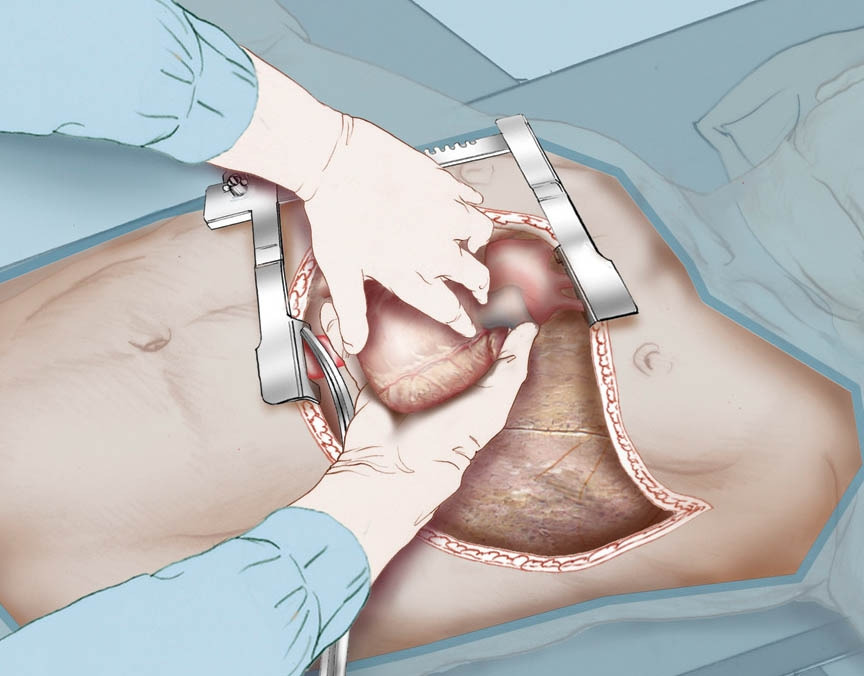

응급실에서 소생치료를 받던 환자의 맥박이 갑자기 잡히지 않아서, 외상외과 전문의가 긴급하게 갈비뼈 사이를 절개하고 열어젖힌 다음에 흉강 내에 손을 집어넣어 직접 심장 마사지를 함과 동시에 환자 침대를 밀면서 수술실까지 달려갔으나, 결국 환자의 맥박이 돌아오지 않아서 수술대 위에서 사망선고가 내려졌다고 했다.

Internal_Cardiac_Massage_R.jpg 응급 흉강 절제술 및 직접 심장 마사지